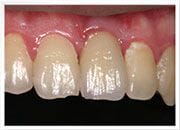

治療後